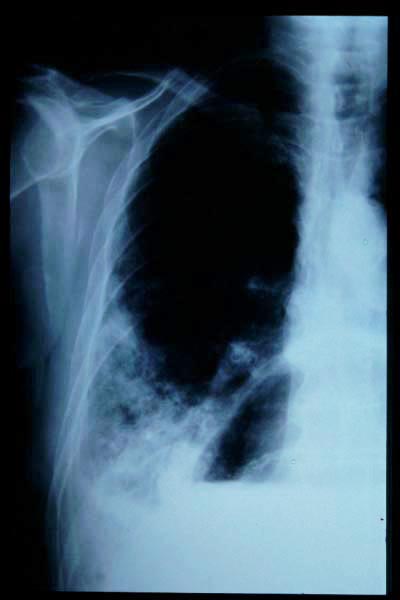

Fractura impactada de húmero .